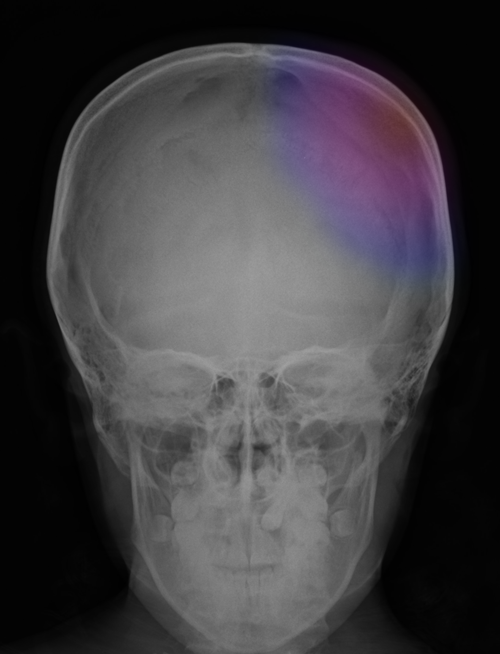

Ως κρανιοεγκεφαλικές κακώσεις ορίζονται οι τραυματισμοί του κρανίου και του εγκεφάλου. Ο όρος κρανιοεγκεφαλική κάκωση συμπεριλαμβάνει ένα ευρύ φάσμα βαρύτητας και αιτιολογίας, από την ήπια διάσειση εγκεφάλου έως τα κατάγματα του κρανίου με συνοδά αιματώματα (επισκληρίδια, υποσκληρίδια και ενδοεγκεφαλικά) και βαρύ εγκεφαλικό τραυματισμό. Η ταξινόμηση και αξιολόγηση τους είναι σύνθετη ανάλογα με το μηχανισμό πρόκλησής τους, την μορφολογία τους (ανοιχτές-κλειστές) και την βαρύτητά τους (ήπιες, μέτριας βαρύτητας και βαρείες). Τα συμπτώματά τους παρουσιάζουν επίσης μεγάλη ποικιλία ανάλογα με το είδος και το βαθμό του εγκεφαλικού τραυματισμού, από την βραχεία διαταραχή του επιπέδου συνειδήσεως έως το κώμα και το ίδιο φυσικά ισχύει για την πρόγνωση και θεραπεία τους. Στην ενότητα αυτή θα δοθεί έμφαση περισσότερο στις ηπιότερες, κλειστού τύπου κακώσεις. |